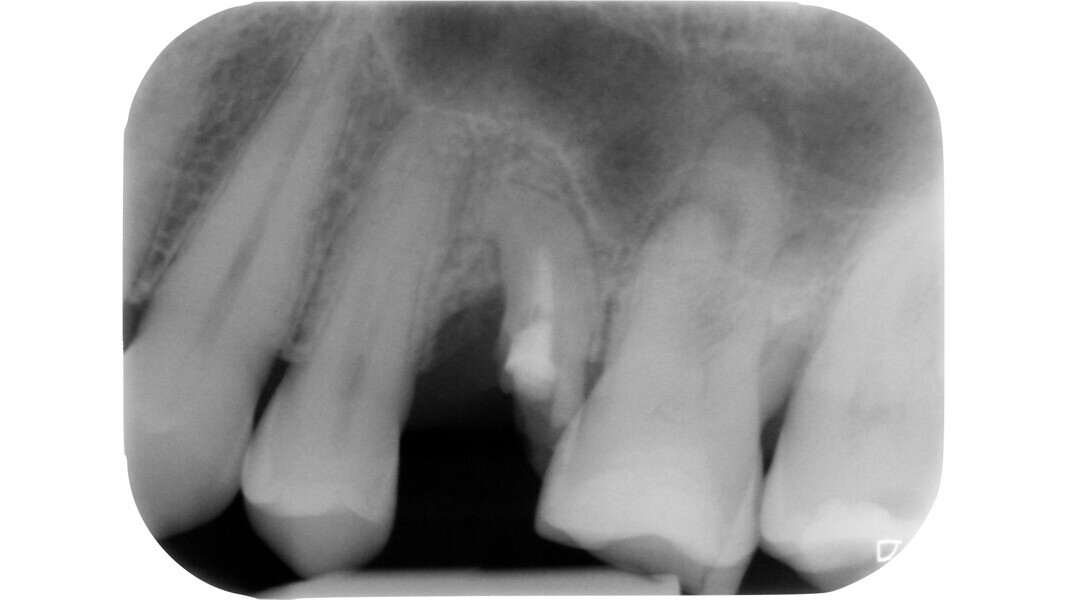

L’étape suivante est la phase de localisation et celle-ci peut s’avérer très difficile, surtout dans les dents calcifiées. Dans ce cas, le praticien doit laisser de côté les instruments rotatifs diamantés et recourir à divers dispositifs spéciaux.

La loi du changement de couleur peut être utile lors de l’approche des canaux calcifiés, puisque le praticien peut constamment distinguer les parois plus claires de la cavité pulpaire du plancher plus sombre et donc, rechercher les orifices dans cette dernière zone. Cette caractéristique est constante et sert de guide durant l’exploration des dents sclérotiques.